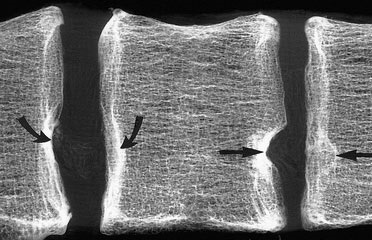

multiple hernii

Găsirea mai multor defecte uzuratsii (ca radiologi descrise SHmorlja hernia) este un semn indirect al patologiei Scheuermann, care este o astfel de boala degenerativă grea, care este format din motive necunoscute, adolescenți, caracterizate prin dezvoltarea cifozei toracice progresive, gipolordoza lombare.

Alte cauze includ cartilagiu predispozitia genetica si tesutul osos al coloanei vertebrale, lipsa de calciu în organism.

Aceste hernii sunt adesea cauza tulburărilor motorii ale capacității coloanei vertebrale, pot fi asimptomatice.

Foto: multiple SHmorlja hernie